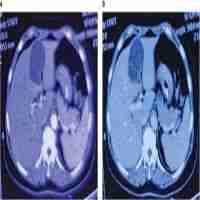

| Abstract | Background Cholecystohepatic duct is a rare anomaly of the biliary system which involves drainage of bile into the gallbladder which may be associated with agenesis of the common hepatic duct or common bile duct. Case presentation A 2.5-month-old infant presented to our emergency department with icterus. He had a history of esophageal atresia and imperforate anus which had been treated surgically by thoracotomy, esophagostomy, gastrostomy and colostomy placement. Following imaging studies by ultrasound and MRCP, the diagnosis of common hepatic duct agenesis was made. Cholecystohepatic duct was present as the solitary drainage pathway of bile from the intrahepatic to extrahepatic biliary system. Conclusions Cholecystohepatic ducts need a high index of suspicion to be diagnosed on preoperative hepatobiliary imaging. As they may be asymptomatic, they are predisposed to iatrogenic injury during hepatobiliary surgeries. |